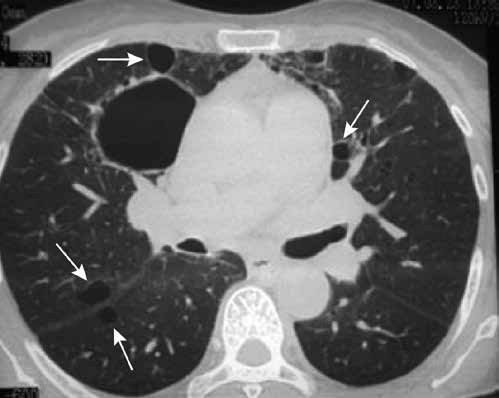

Tipo de patrón frecuente en enfermedades granulomatosas:

Nodular

Un nódulo solitario es frecuente por enfermedad:

Granulomatosa por tuberculosis

Muchos nódulos indican:

Metástasis